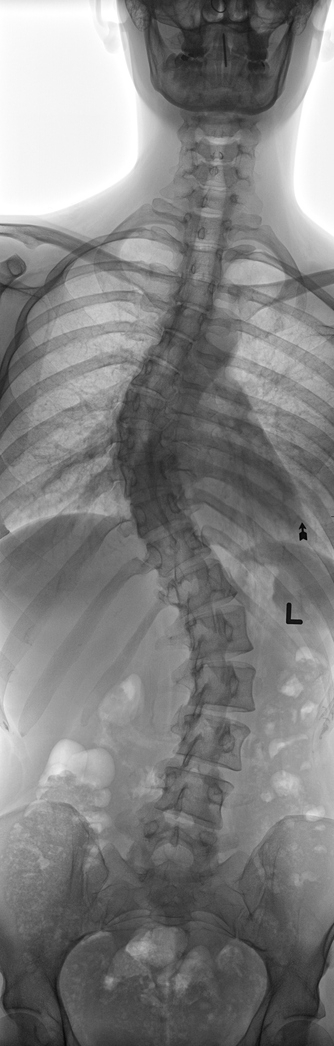

▲척추가 C자 혹은 S자로 휘는 척추측만증(출처=게티이미지뱅크)척추가 'C자' 혹은 'S자'로 휘어지는 척추측만증으로 병원을 찾는 이들이 끊이지 않는다. 인구의 약 8%가 척추측만...